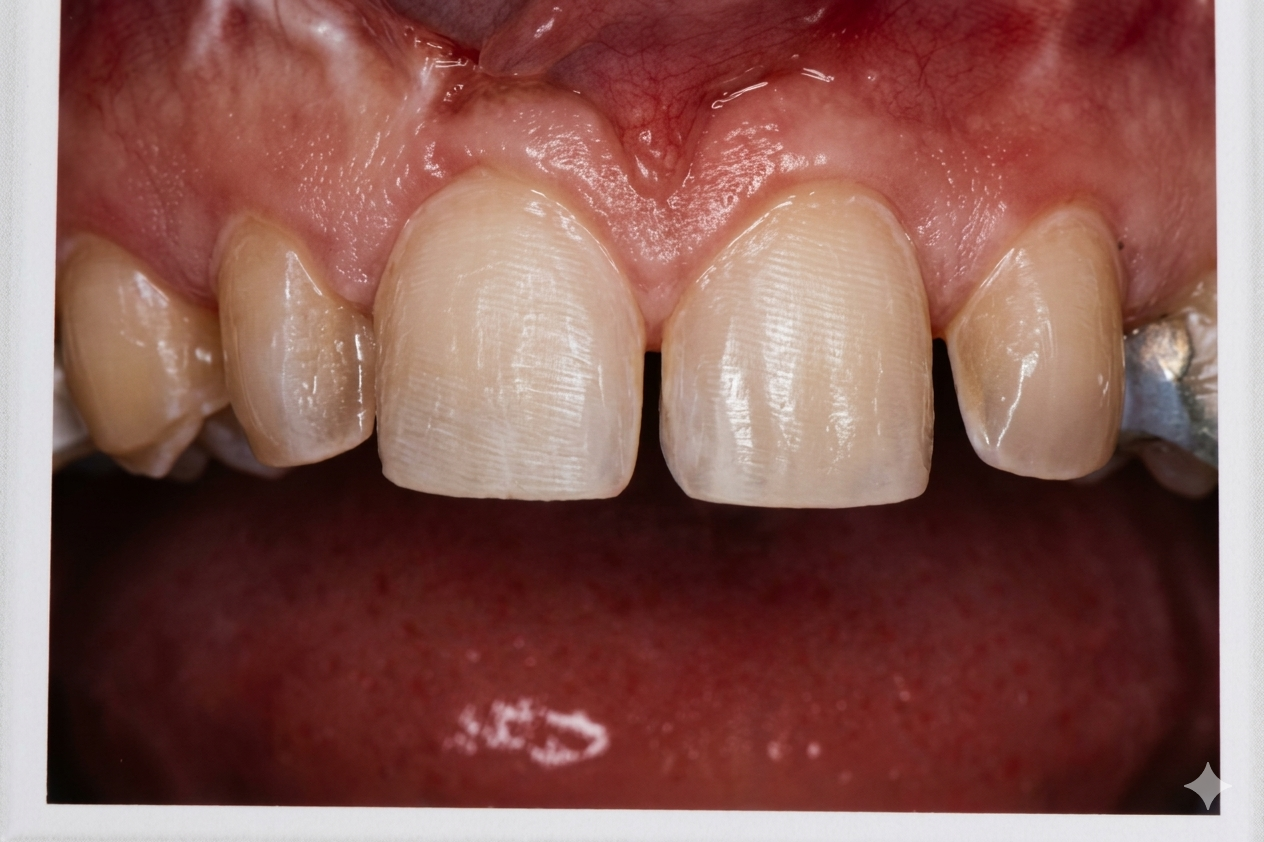

crown lenthening